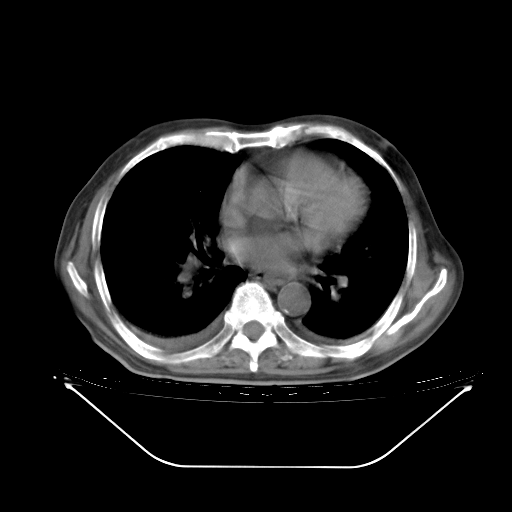

今天复查肺部CT,发现双肺广泛磨玻璃样改变。所以我把3月19日和5月9日相隔50天的肺部CT上传。请大家会诊。

5月9日肺部CT(在4月27日齐鲁医院肺部CT描述部分肺组织磨玻璃样改变,12天后肺组织广泛磨玻璃样改变)

大致读了系列胸部CT:纵隔窗无明显异常,肺窗:从4、27至今:主要是双肺中下野外带可见毛玻璃样改变,目前处于急性肺泡炎阶段,至于原因考虑1、结替组织或胶原血管性疾病所致?2、恶性疾病如恶组在肺部所致的表现或细支气管肺泡癌?3、药物或其它原因如肺蛋白沉着症所致肺泡炎目前不太可能?总之,明天就去请我院的呼吸科、感染科、血液科和临免专家会诊哈。